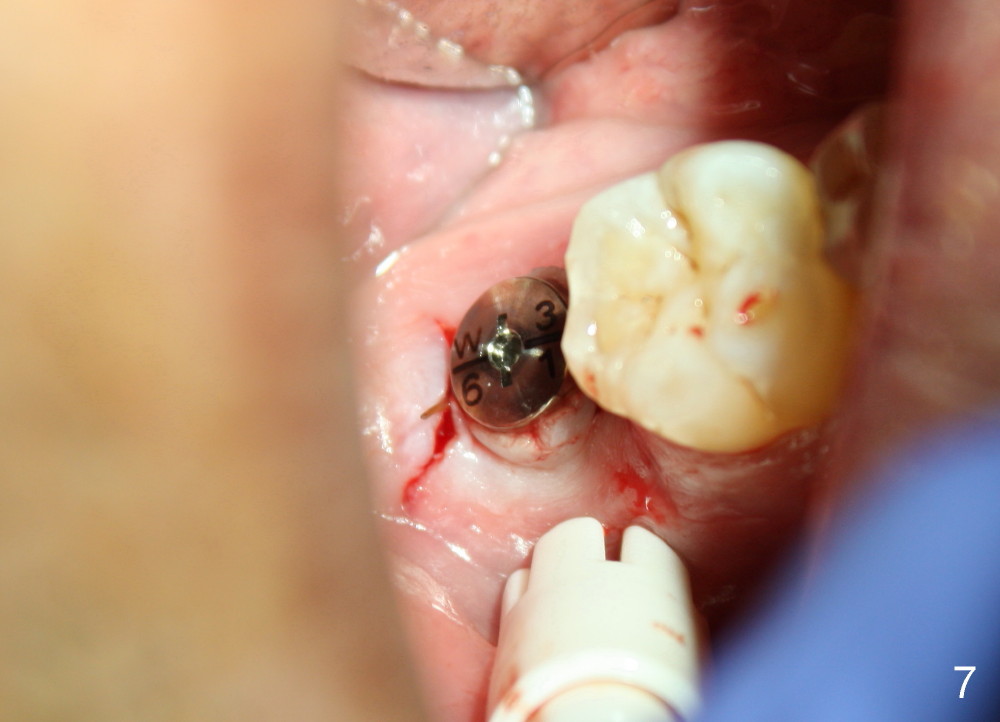

The implant is placed in the middle of the ridge buccolingually (Fig.6). A 6.2 x 3 (1) mm healing abutment is placed; the flaps tightly adapt to the abutment following suturing (Fig.7). The wound is then covered by perio dressing.